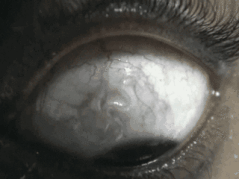

p>眼睛寄生虫以 a href="#" data-lemmaid="3224299">裂头蚴 /a>和猪

裂头蚴病

裂头蚴可在体内移行,并侵犯多种组织器官,产生的症状远较成虫严重.